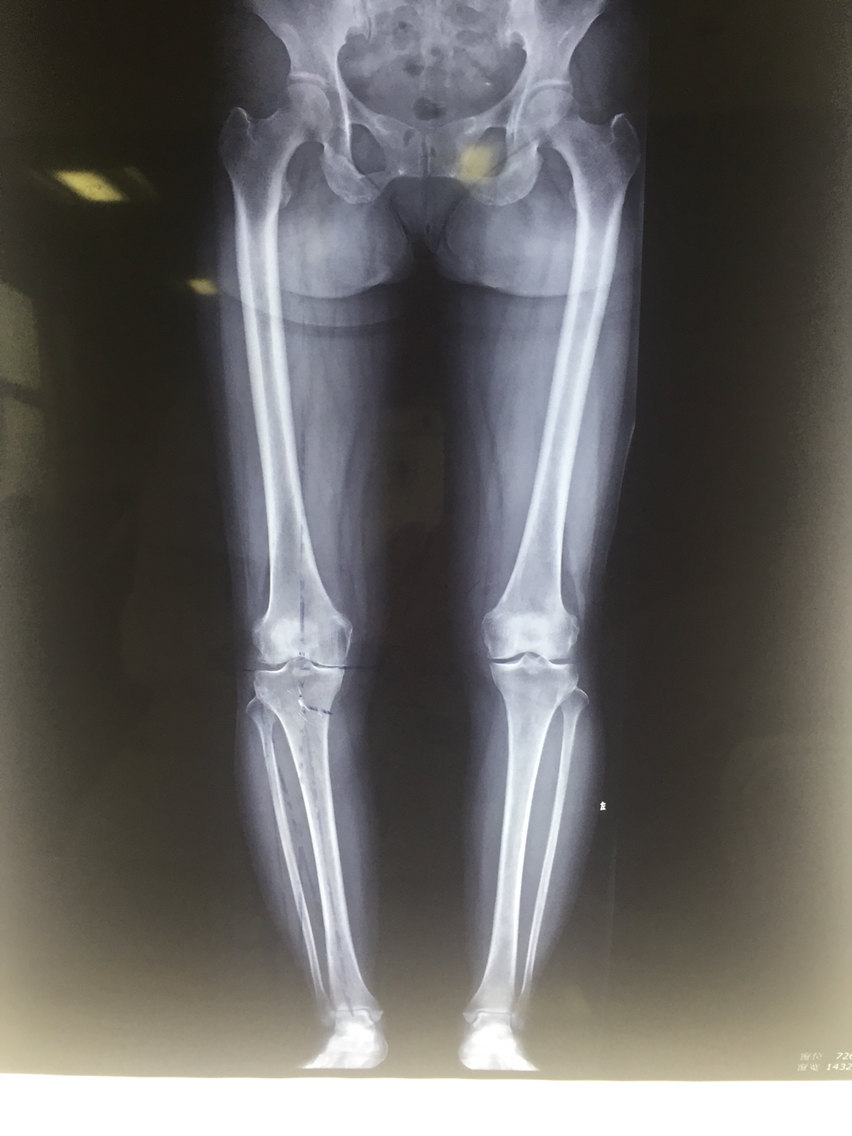

陶旭博士还谈到,骨性关节炎初期x光检测常常正常。但稍后渐渐出现关节间隙窄小,反映覆盖在皮质上的关节骨膜层变薄。最后,骨性关节病进行性发展,关节间隙显著变窄,关节缘变锐,于边沿出现骨刺或骨赘产生男性膝盖疼痛可能有三种病,内外踝变尖。骨膜下骨增厚和硬化,于骨膜下骨受压最大部位发生骨脓肿。关节内骨膜剥,骨质崩裂步入关节,产生关节内游离体。晚期关节骨膜显著破坏,骨端变型,关节面凸凹不平。